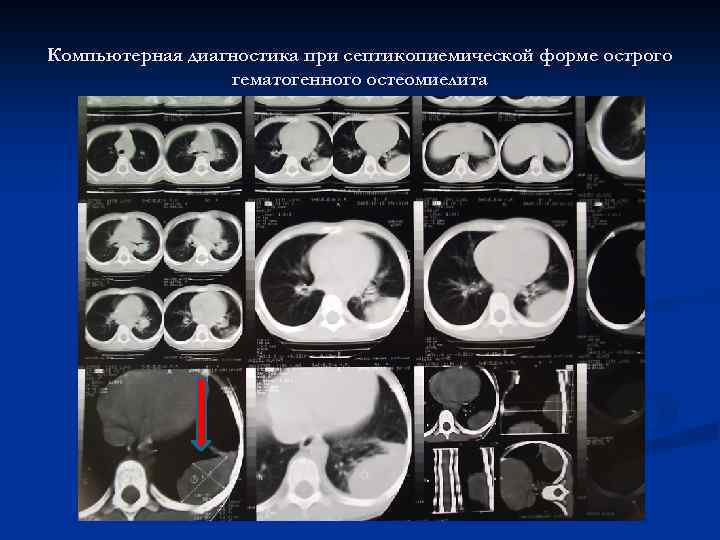

Септикопиемическая форма острого гематогенного остеомиелита

Компьютерная диагностика при септикопиемической форме острого гематогенного остеомиелита